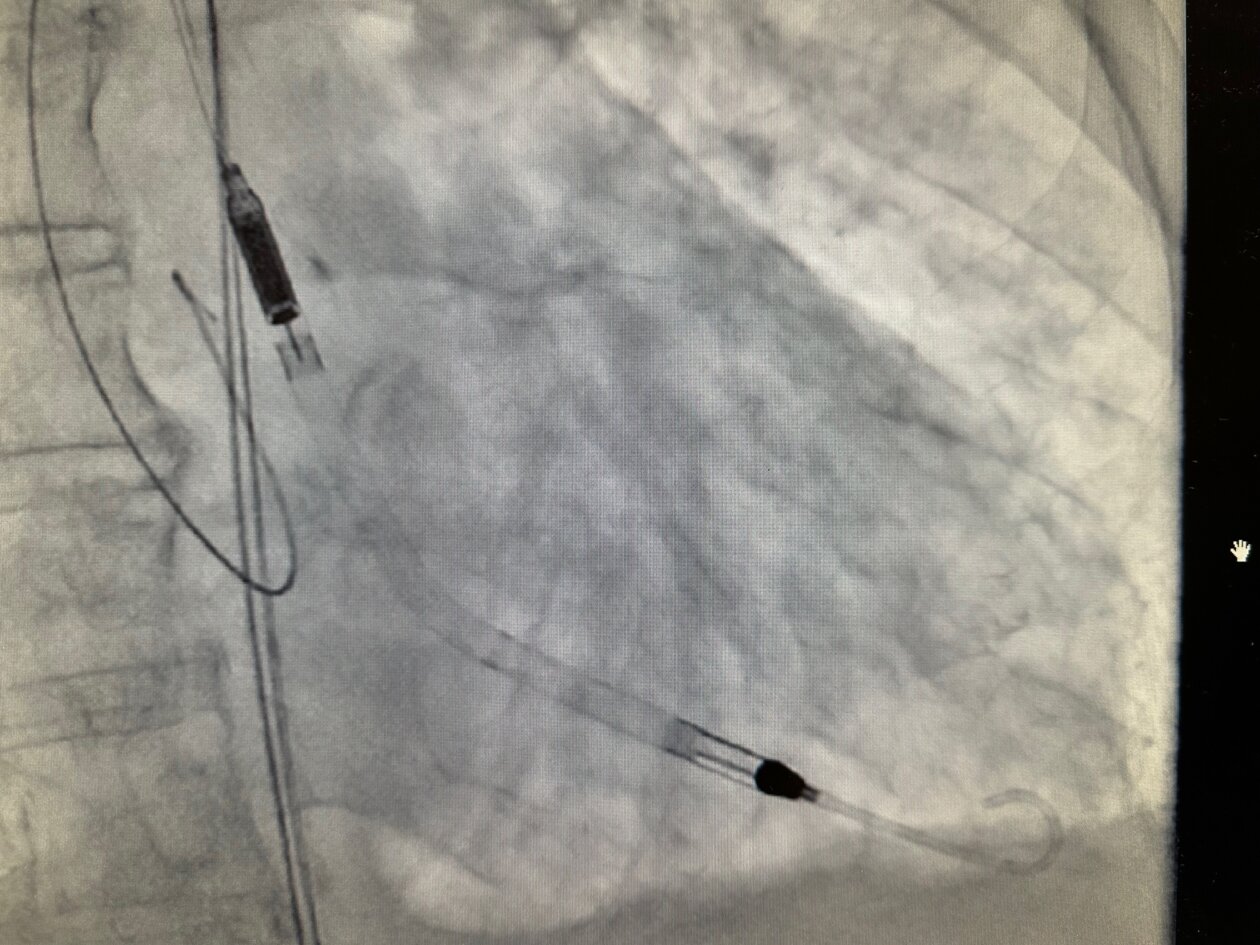

“Impella CP koristi tehnologiju perkutane srčane pumpe koja se kroz femoralnu arteriju uvodi u lijevu srčanu klijetku i pruža potporu radu srca kod visokorizičnih zahvata i srčanog zatajenja. Uređaj osigurava protok krvi do 4.3 litre u minuti, čime značajno smanjuje opterećenje srca i pomaže pri održavanju cirkulacije.

Ova tehnologija predstavlja vrhunac suvremene medicinske skrbi za pacijente u kardiogenom šoku ili pri izvođenju visokorizičnih PCI zahvata.